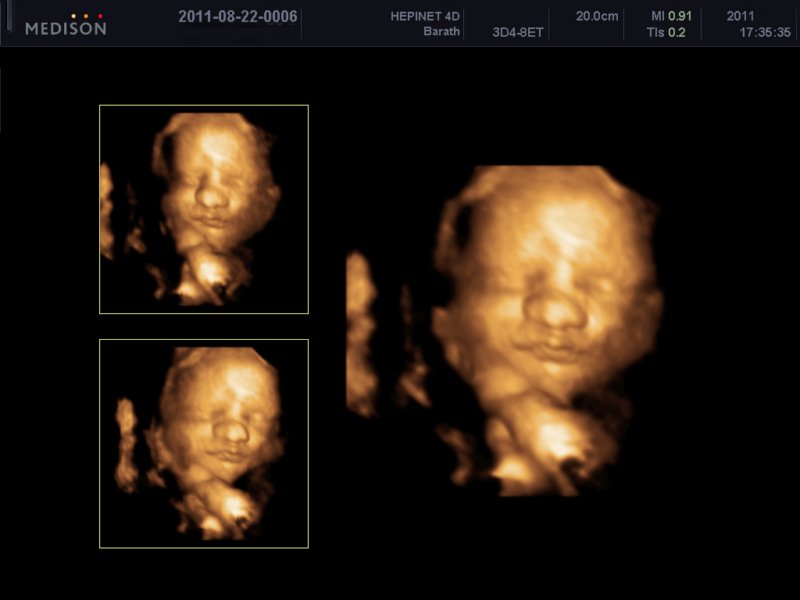

Barokk angyalka